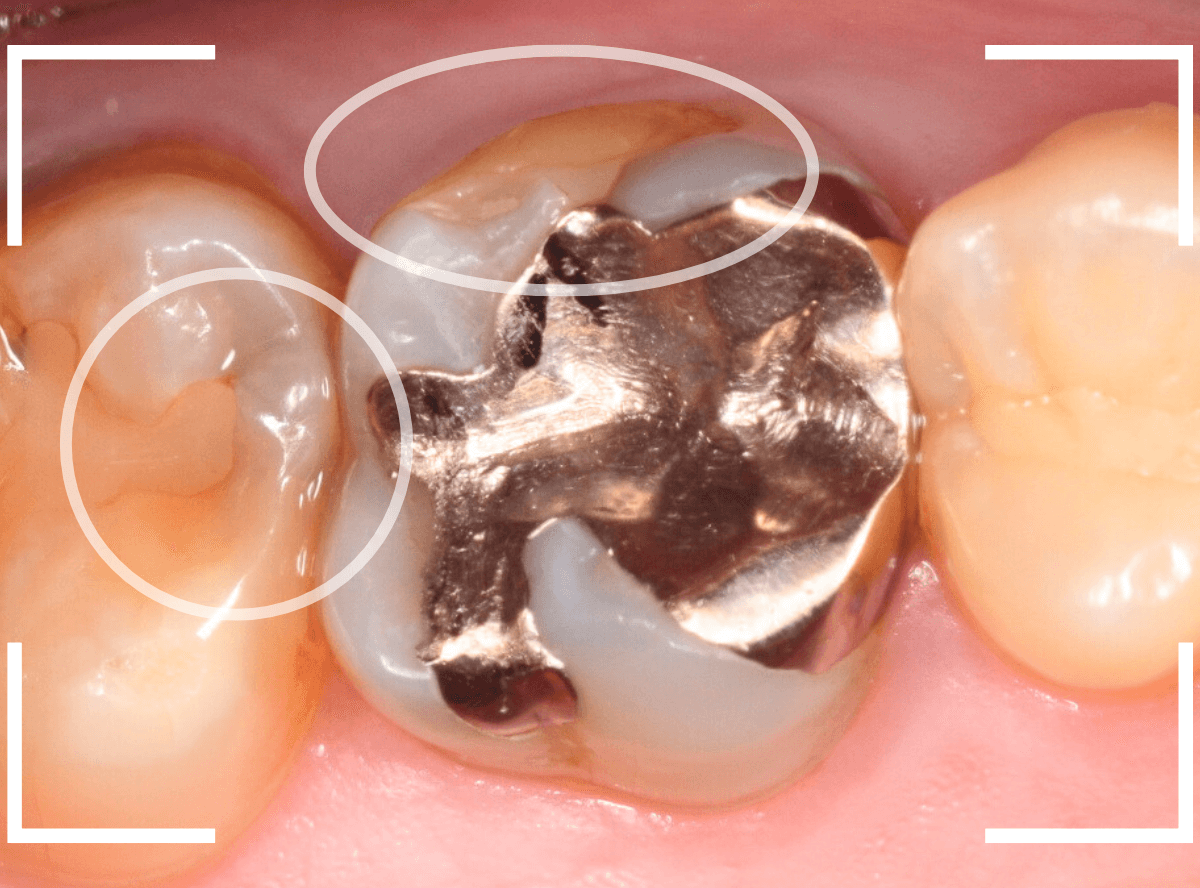

Case.16 金属の周りであちこちから虫歯

検診を希望された患者さんのケースです。

お口の中を拝見すると、上の奥歯の歯のすき間(隣接面)や、変色したレジンの中が怪しい感じです。

レントゲン写真で確認します。

青い線が神経で、赤い線が虫歯と思われる部分です。

奥から3歯が虫歯と思われますが、特に中央の歯の虫歯が深そうです。

まず、中央の歯の金属を除去します。

〇部分は前の治療時にしいたセメントです。この下に虫歯が広がっていると思われます。

セメントを除去したところです。

赤く染め出されているところが虫歯です。

神経に近くなっていますので、診療に虫歯を除去します。

側面のレジンや隣の歯との間の虫歯も慎重に除去します。

かなり広く虫歯が広がっています。

奥の歯の虫歯も全て除去しました。

3歯すべての虫歯を除去したところです。

しばらくお薬をつめて症状を経過観察した後、型どりをしてつめものを再製作する予定です。